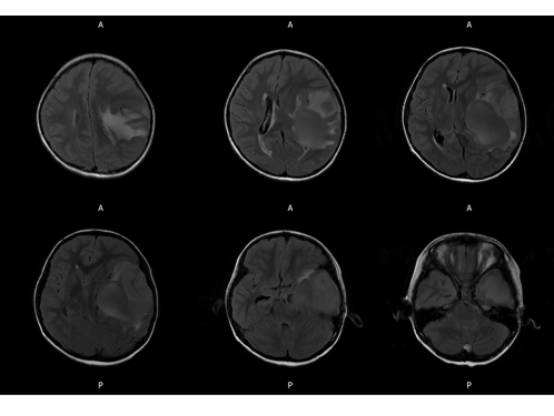

MR平扫及增强示:

MR

左侧颞叶见大块状等长T1等长T2异常信号,FLAIR呈高新,DWI(b=1000)实质部分呈稍高信号,ADC实质部分呈等信号,边界尚清,周围脑实质受压。注入GD-DTPA后病变实质部分呈明显强化。